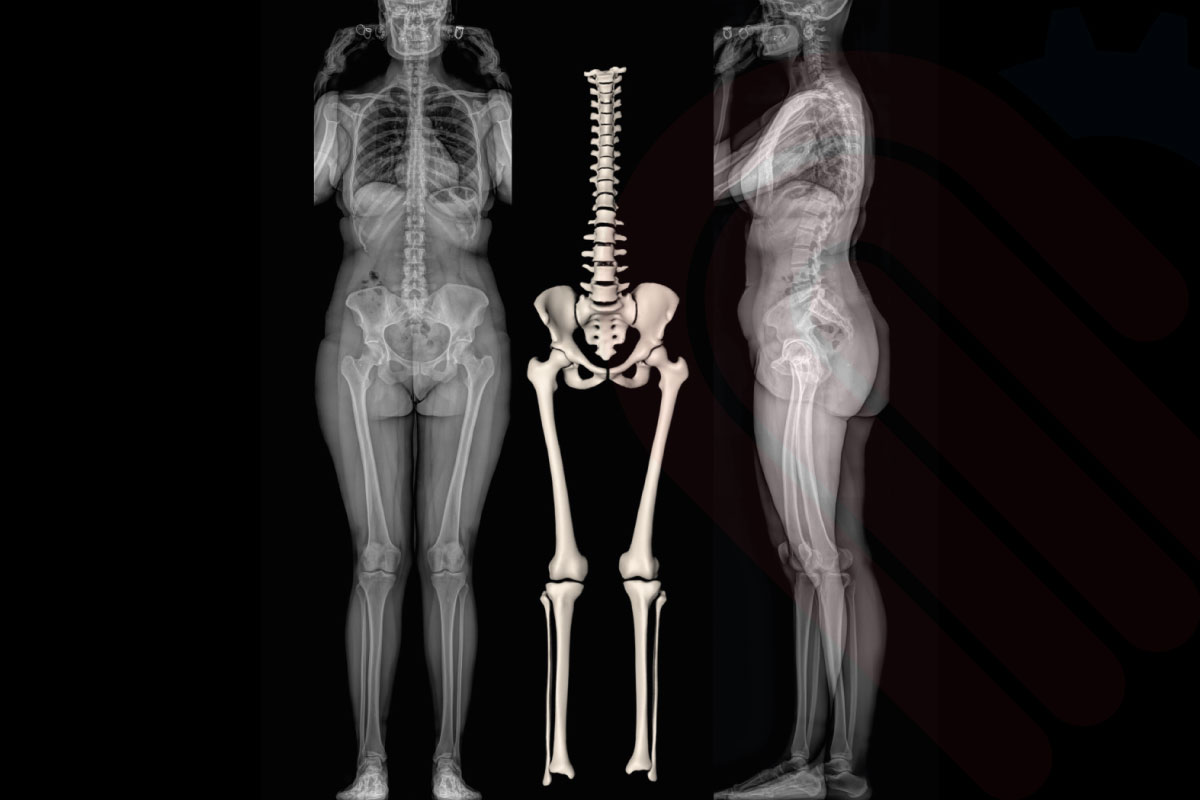

EOSedge, çekilen biplanar görüntülerden 3 boyutlu anatomik modeller oluşturabilme yeteneği ile öne çıkar. SterEOS yazılımı ile entegre çalışan sistem, hastanın iskelet yapısını milimetrik doğrulukla modelleyerek cerrahi planlamayı güçlendirir. Bu sayede omurga deformitelerinin, eklem bozukluklarının ve alt ekstremite hizalanma sorunlarının ayrıntılı şekilde değerlendirilmesi mümkün olur.

SterEOS ile elde edilen 3D modeller, yalnızca statik analiz değil, aynı zamanda postoperatif sonuç tahmini ve farklı cerrahi senaryoların simülasyonu için de kullanılabilir. Klinik araştırmalar, EOS tabanlı 3D modelleme ile yapılan planlamaların, postoperatif sonuçlarla yüksek oranda uyum sağladığını göstermektedir*.

SterEOS 3D Analysis, EOSedge görüntülerini kullanarak omurga, pelvis ve alt ekstremitelerin milimetrik doğrulukla üç boyutlu rekonstrüksiyonunu sağlayan gelişmiş analiz yazılımıdır. Bu sistem, biplanar düşük doz görüntülerden anatomik referans noktalarını otomatik olarak belirler ve hastanın gerçek boyutlarına sadık, ölçülebilir 3D modeller oluşturur. Klinik olarak skolyoz, dejeneratif omurga hastalıkları, ortopedik deformiteler ve protez planlaması gibi alanlarda yüksek doğrulukta analiz imkânı sunar.

Araştırmalar, 3D analiz ile elde edilen ölçümlerin konvansiyonel 2D yöntemlere kıyasla %95’in üzerinde tekrarlanabilirlik sağladığını göstermektedir*.

spineEOS, EOSedge ile elde edilen düşük doz biplanar görüntüleri kullanarak omurga deformitelerinin 3D planlamasını sağlayan ileri düzey bir yazılımdır. Cerrahlar, hasta ayakta veya oturur pozisyonda iken alınan gerçek boyutlu görüntüler üzerinden, sagittal ve koronal düzlem analizlerini yapabilir, tedavi sonrası beklenen omurga hizalanmasını simüle edebilir. Özellikle skolyoz ve kifoz cerrahilerinde, implant yerleşim açılarından segmental hizalanmaya kadar çok sayıda parametreyi önceden değerlendirme imkânı sunar. Klinik çalışmalar, spineEOS kullanılarak yapılan preoperatif planlamaların, cerrahi sonrası hizalanma doğruluğunu anlamlı ölçüde artırdığını göstermektedir*.